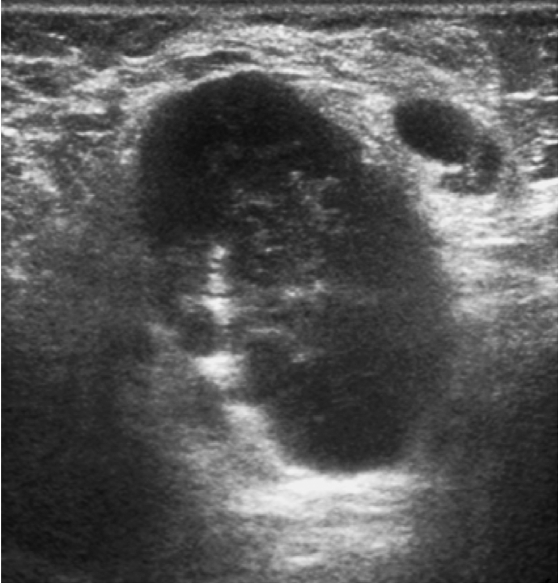

Наиболее удобным, доступным и хорошо изученным методом оценки статуса регионарных лимфатических узлов является УЗИ, при котором возможно оценить форму, контуры и структуру измененных лимфатических узлов. Для метастатических изменений характерна округлая и неправильная форма лимфатического узла (встречаются в 79% наблюдений); рис. 1. Также могут выявляться метастазы в лимфатических узлах с измененным корковым слоем, который проявляется его неравномерным утолщением или выбуханием контура на отдельном участке (рис. 2). Структура метастатически измененных лимфатических узлов многообразна и может быть гипоэхогенной, анэхогенной, гиперэхогенной, гетерогенной, с кальцинатами и даже с включениями жидкостного характера (рис. 3).

Рис. 2. Метастатические изменения подмышечного лимфатического узла в В-режиме: отмечается неравномерное утолщение коркового слоя с выбуханием контура на отдельном участке.

Fig. 2. B-mode ultrasound image of metastatic axillary lymph node: diffuse thickening of the cortex and cortical bulging of a separate part.